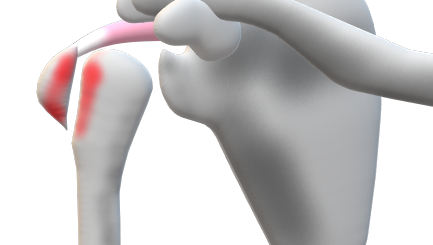

合併症

・肩関節脱臼

・腋窩神経損傷

・腋窩動脈損傷

・関節不安定性

整復前の合併症確認

・腋窩動脈損傷⇒橈骨動脈の拍動確認

・腋窩神経損傷⇒三角筋部の感覚確認